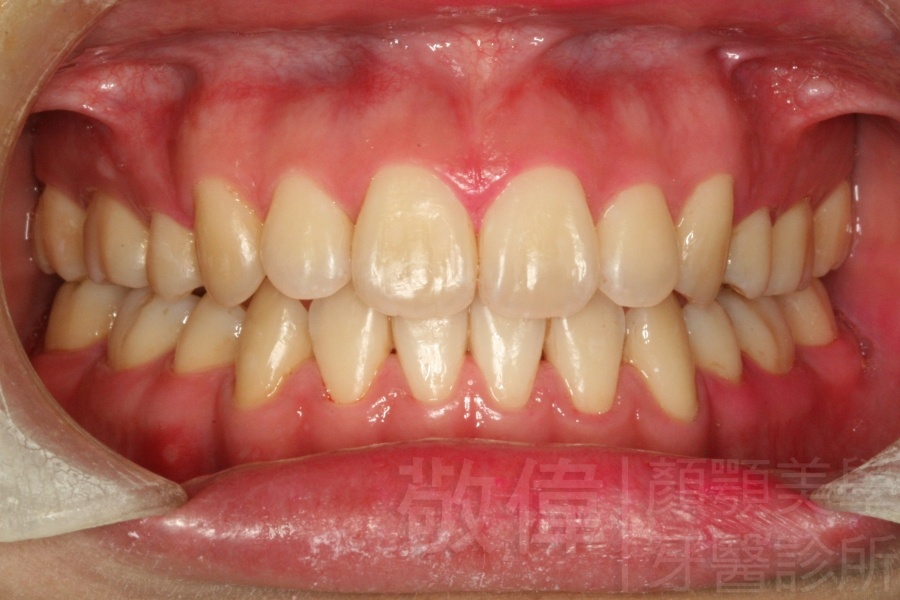

變臉矯正,原來戽斗妹跟大歪臉變成自信正妹

經由本院3D數影X光影像儀分析、與3D齒顎顏矯正技術,再配合口腔顎面正顎專科醫師施以正顎手術治療,雙方共同合作,使患者臉部外觀有很好的改善,大歪變小歪,產生了天南地北的大改變,她的人生也整個變得不一樣。

因為矯正與正顎手術的配合,使「戽斗妹」變成了「陽光正妹」,完全的改變了她的人生,在面對各種場合、與人交際都散發出自信微笑。所以,奉勸家長,如果小朋友有臉顎畸型的問題,應該考慮配合做這種簡單、安全、有效的正顎手術。

「3D齒顎顏矯正」,不止矯正您的牙齒,也會改變您的人生。「治療前」和「治療後」出社會的人生際遇一定會截然不同。